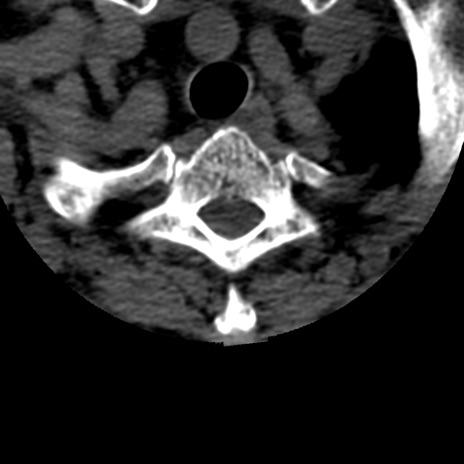

症例50 頚椎CT(横断像)

頚椎CT